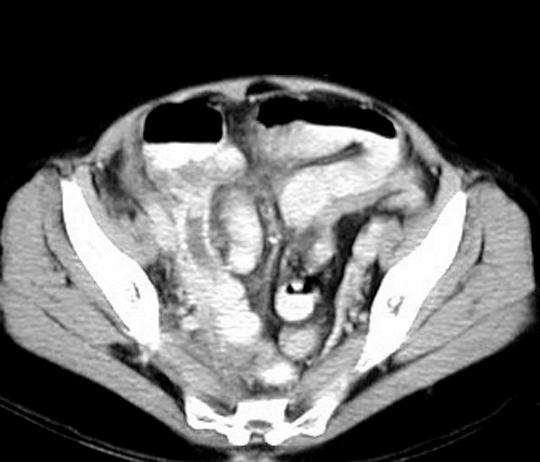

CT: Highly accurate

Signs: